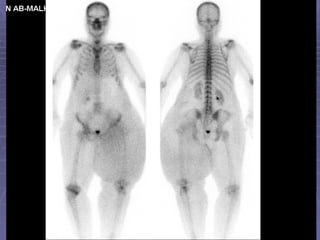

Metastatic Bone Disease Bone scan is an extremely important tool in decision making during management of cancer patients. Any cancer potentially could cause bone metastatic disease.  However, prostate, breast and lung cancers have propensity to metastasize to bone.

Metastatic Bone Disease and Bone Pain About 80% of patients with known cancer and bone pain have metastases documented by bone scan. 30 – 50% of patients with metastatic bone disease do not have bone pain.

Metastatic Bone Disease and Image Findings The hallmark of metastatic bone disease is multiple foci of increased osteoblastic activity in bony skeleton. However, single lesion could be also metastatic.

Metastatic Bone DiseaseBone scan is an extremely important tool in decision making during management of cancer patients. Any cancer potentially could cause bone metastatic disease. However, prostate, breast and lung cancers have propensity to metastasize to bone.

Metastatic Bone Diseaseand Bone Pain About 80% of patients with known cancer and bone pain have metastases documented by bone scan. 30 – 50% of patients with metastatic bone disease do not have bone pain.

Metastatic Bone Diseaseand Image Findings The hallmark of metastatic bone disease is multiple foci of increased osteoblastic activity in bony skeleton. However, single lesion could be also metastatic.